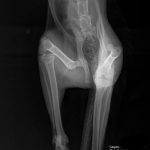

Bizony, Olgácskának már el is érkezett az idő, hogy keressünk neki egy álomcsaládot. Olgának december legelején kértek segítséget, ugyanis elütötte őt egy autó, teljesen lebénult a hátsó lábaira és 2 napig ilyen állapotban volt az utcán. Csodával határos módon 1 hónap alatt szinte teljesen regenerálódott, ugyan a szaladás még nem megy, de járás közben szinte már nem is látszik, hogy mi történt vele nem is olyan rég.